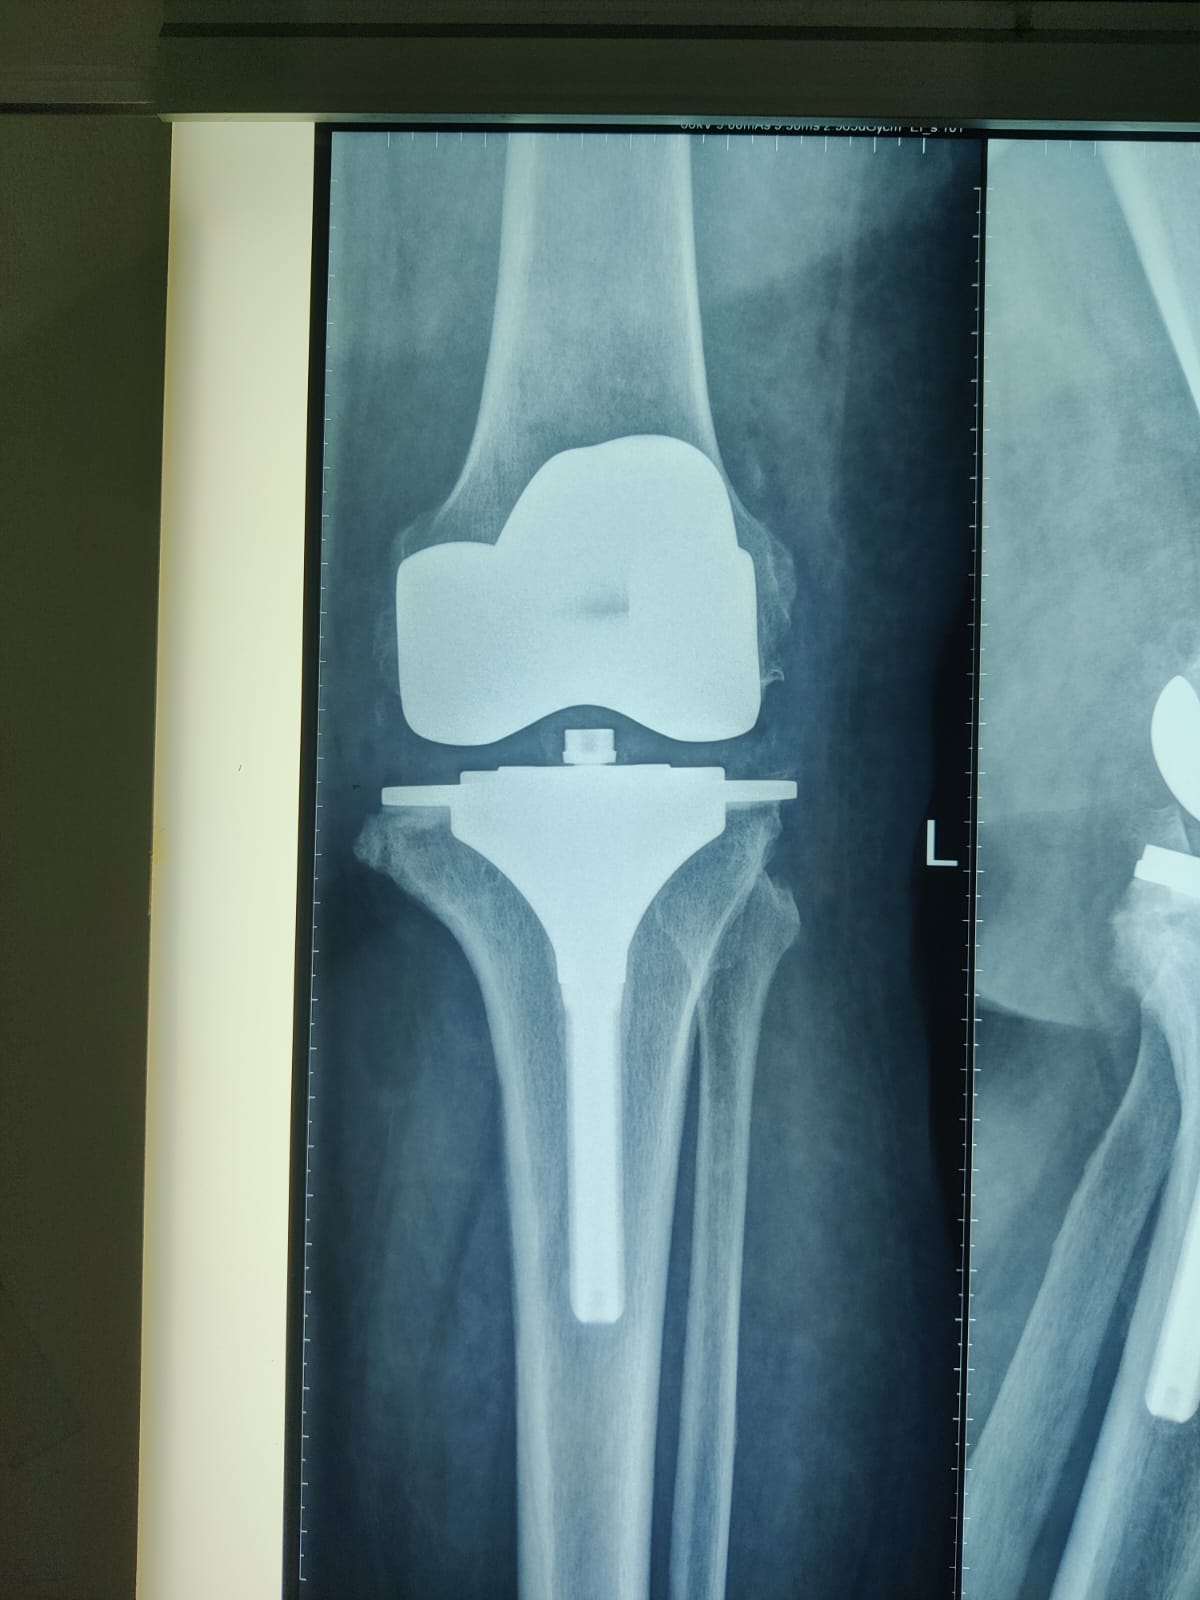

62 year old female with stage 4 OA

Primary Left TKR

Post op images of Right knee